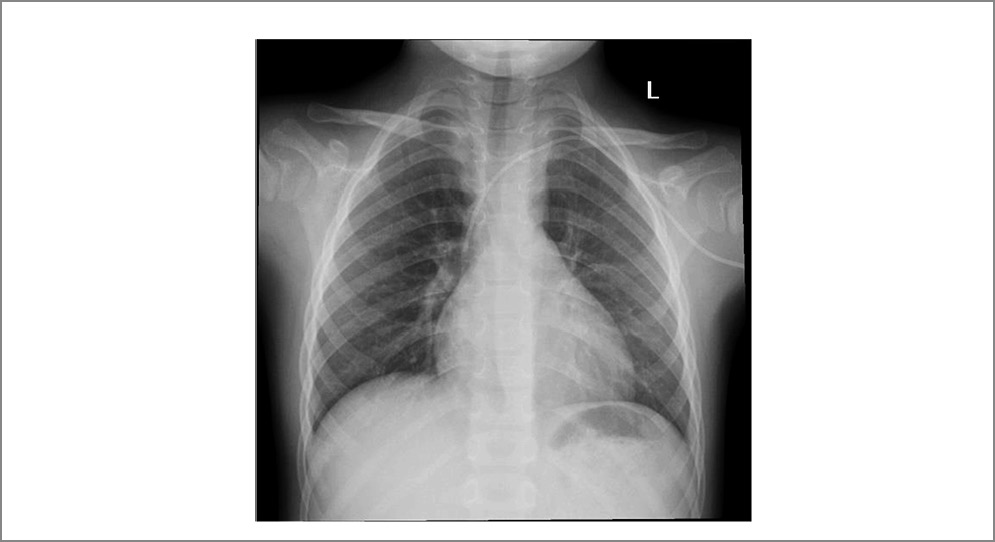

КТ-поражения, характерные для бактериальной инфекции. По данным зарубежных авторов, наиболее характерными изменениями на КТ ОГК для пневмоний бактериальной этиологии являются участки «матового стекла» и зоны консолидации. Так, по данным исследования F. Okada и соавт., у 86 пациентов, инфицированных только S. pneumoniae, наиболее часто встречались участки «матового стекла» (n=74, 86,0%) и консолидация (n=65, 75,6%), затем утолщение бронхиальной стенки (n=22, 25,6%), центрилобулярные узелки (n=17, 19,8%) и ретикулярная непрозрачность (n=8, 9,3%; рис. 4) [23].

Рис. 4. ВП, вызванная S. pneumoniae [23].